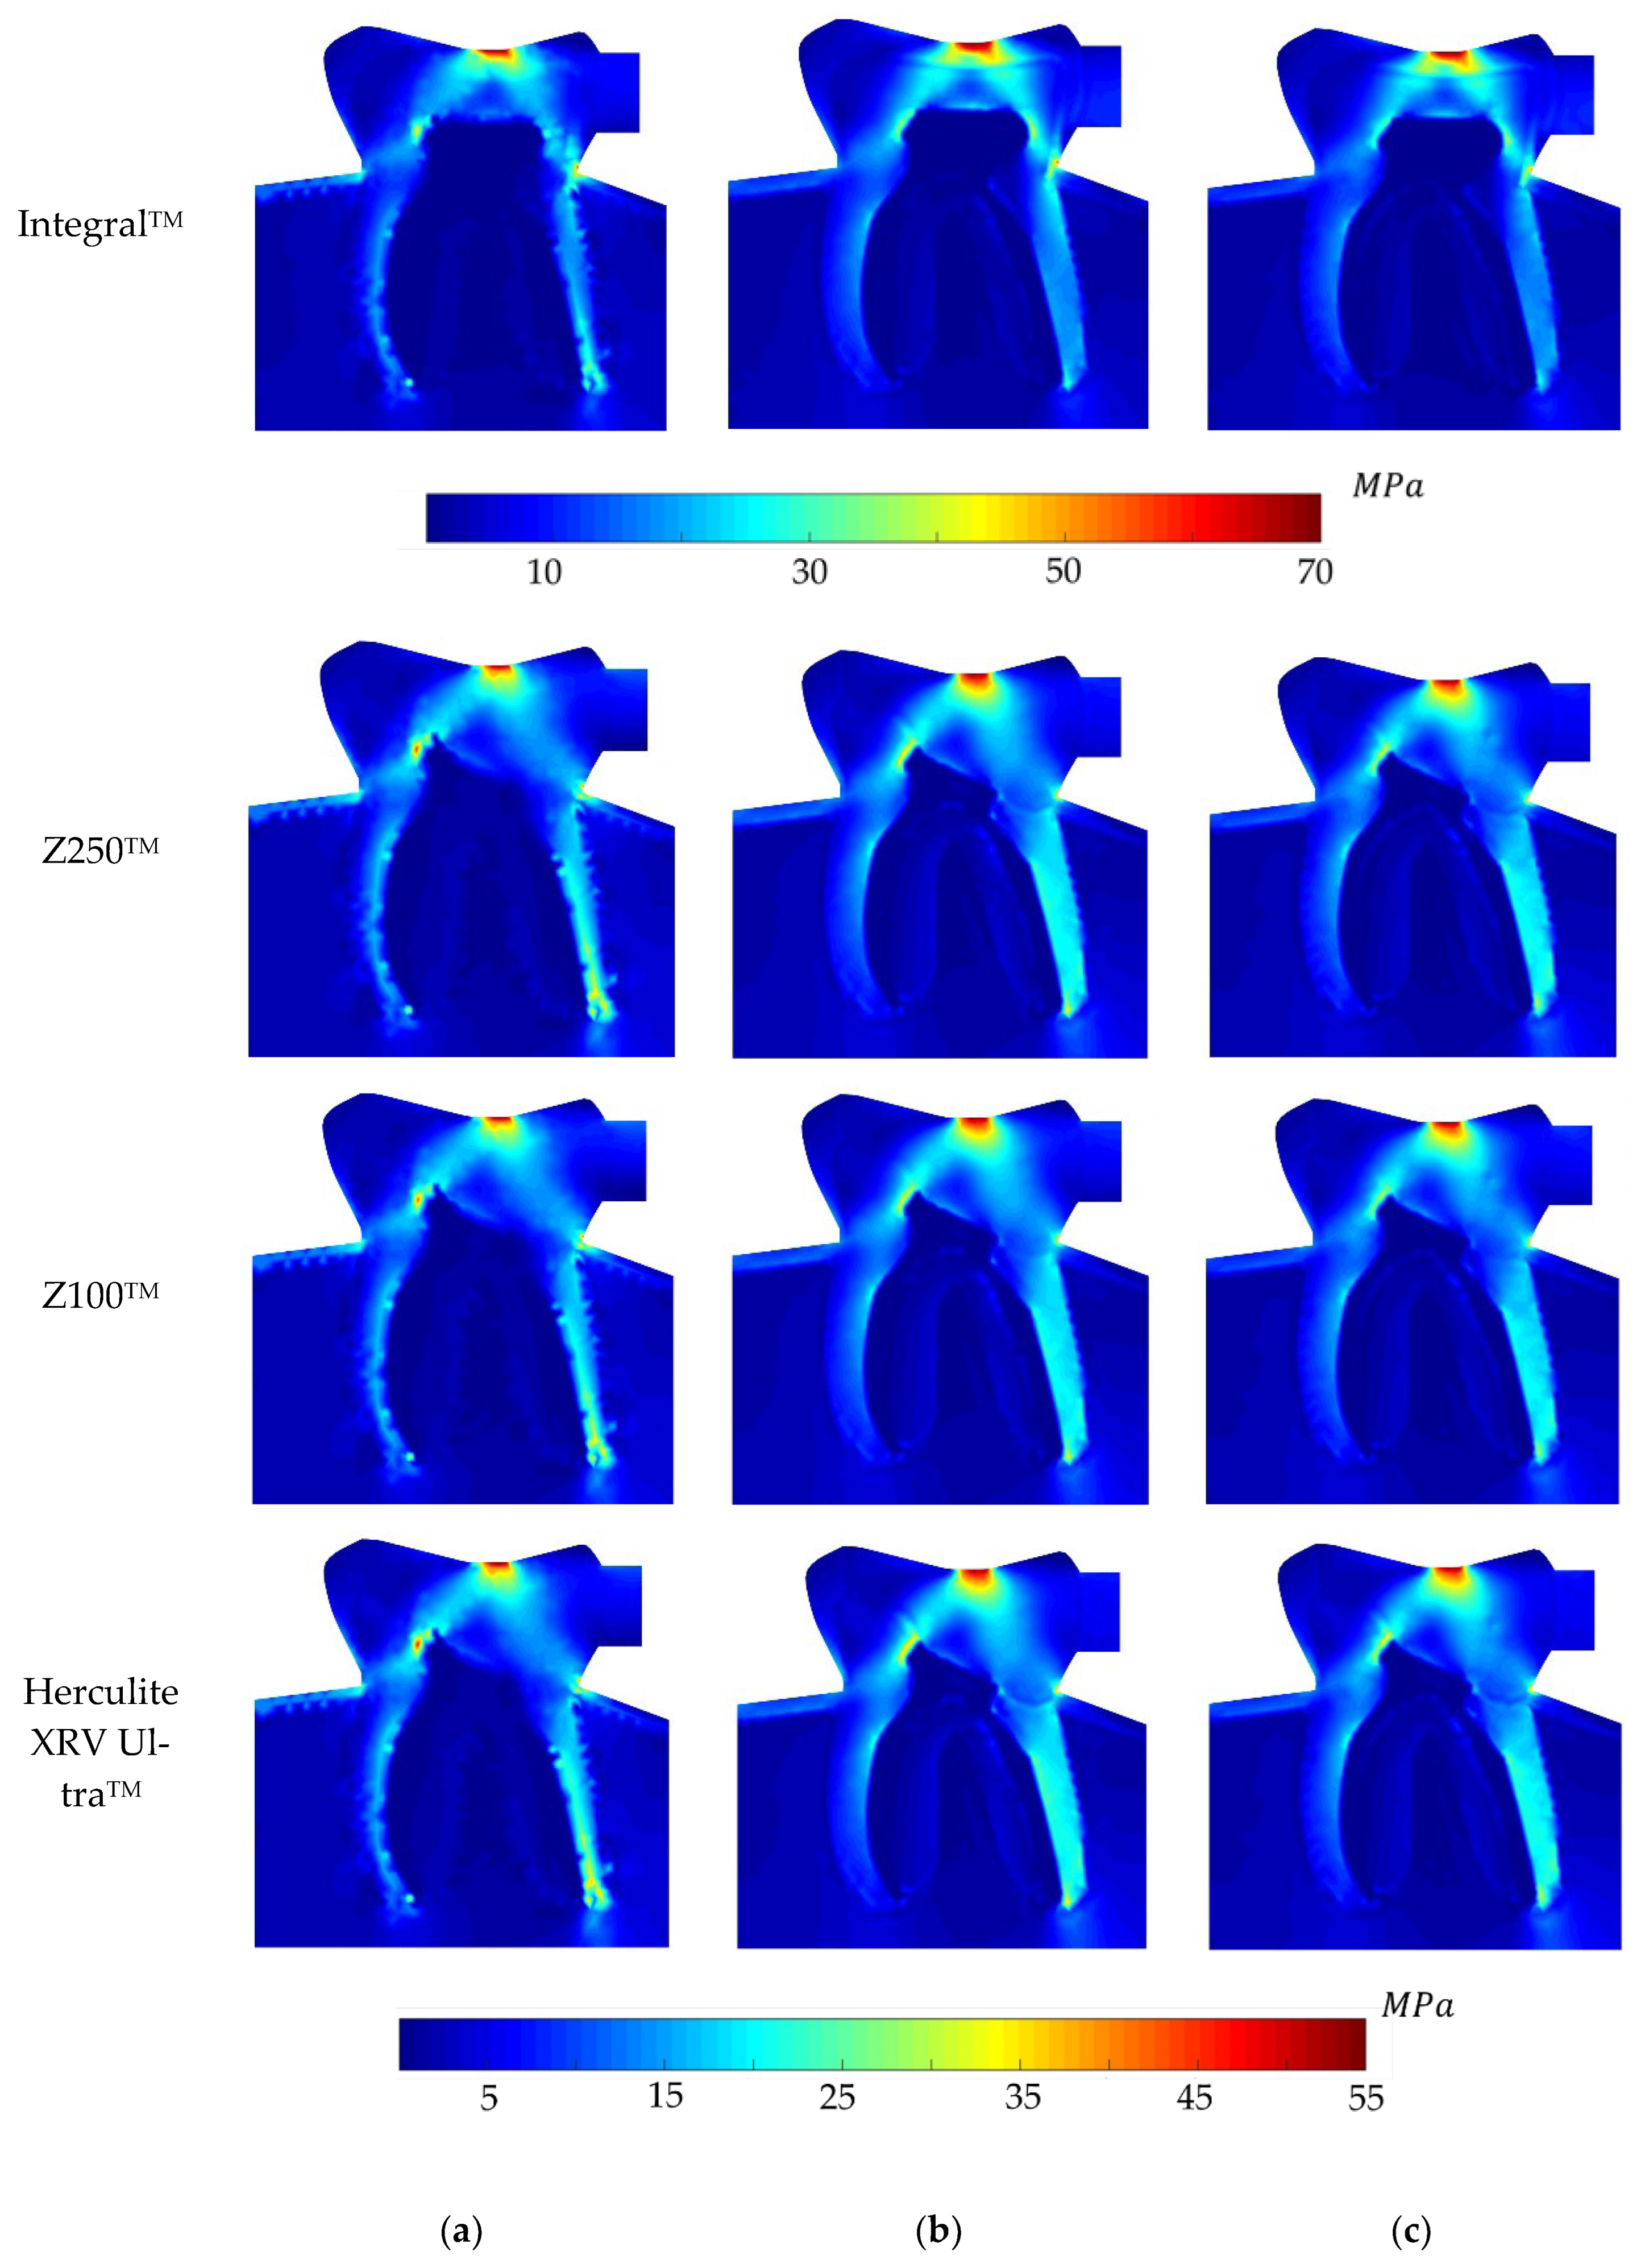

5. Analysis and Results

6. Discussion on the Results

- The non-restored tooth is characterised by enamel rather than composite restoration. Enamel exhibits the highest Young’s modulus compared to the composites. Consequently, an integral tooth demonstrates a greater ability to withstand forces compared to composite restorations. It means that the stiffness of enamel is higher than that of the restorative materials.

- The ranking on the local stress analysis can be rationalised based on the superior mechanical properties of Z100TM, including its elevated Young’s modulus, notably higher tensile and compressive strength compared to other composite materials. This implies that dental restoration using Z100TM results in increased stiffness and rigidity in the treated tooth. It owns the highest percentage of fillers, 66%, which implies higher hardness.

- Herculite XRV UltraTM exhibited the weakest response in terms of elasto-static analysis. One potential reason could be attributed to its lower Young’s modulus and consequently, the lowest hardness, which may be influenced by the presence of barium glass filler in this composite. Conversely, the Zirconia Filler in Z100TM and Filtek Z250TM might account for the improved physical properties observed in these two composites.

- In the depicted stress profiles of the BLV load case, where there is no tooth on the left side of the model (no essential boundary condition), the stress distribution shows higher value on critical regions, mostly close to the boundaries. The absence of essential boundary conditions on the left side of the 2D model in the BLV and OLV load cases leads the applied force to produce a higher level of stress on the borders and critical spots. In this regard, the global stress distribution maps obtained with the meshless methods clearly show the potential rupture lines. This study shows the importance of the neighbour tooth to prevent a potential fracture.